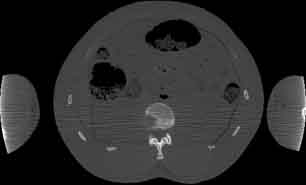

Visible Human male: Sectio transversalis 1622

CT

NMR

Pd                          / T2 \                         T1